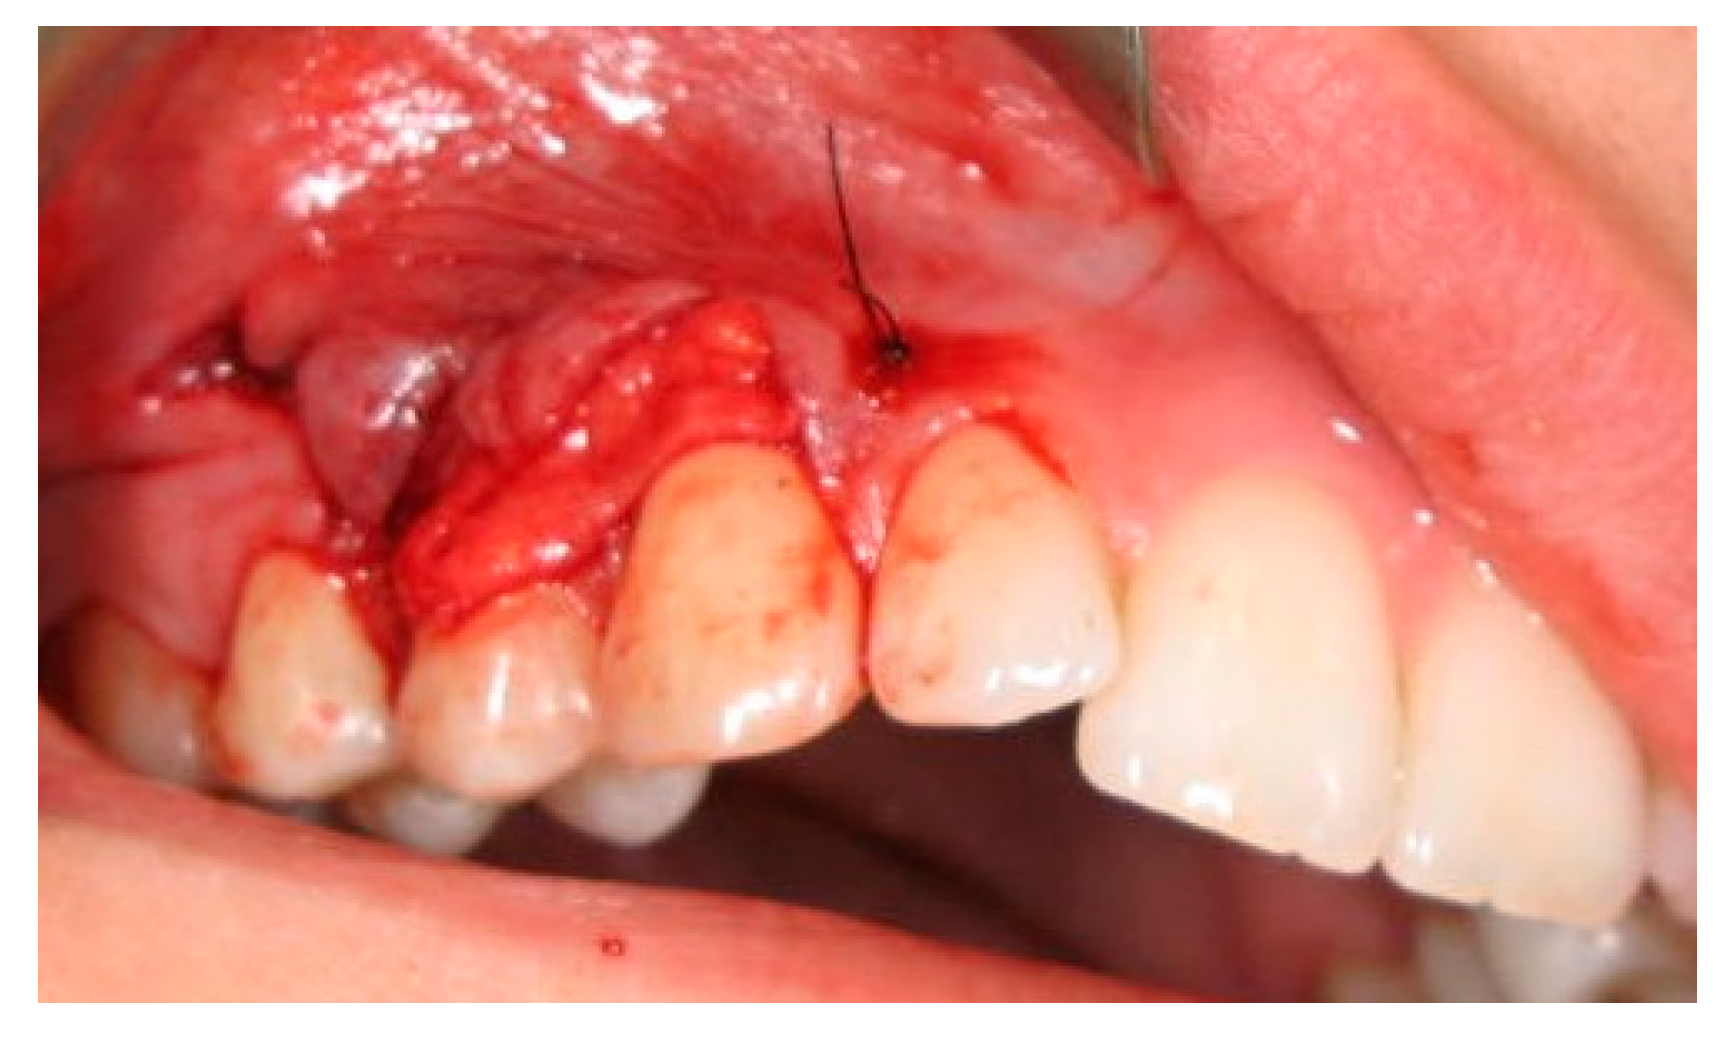

2.3. Surgical Procedures